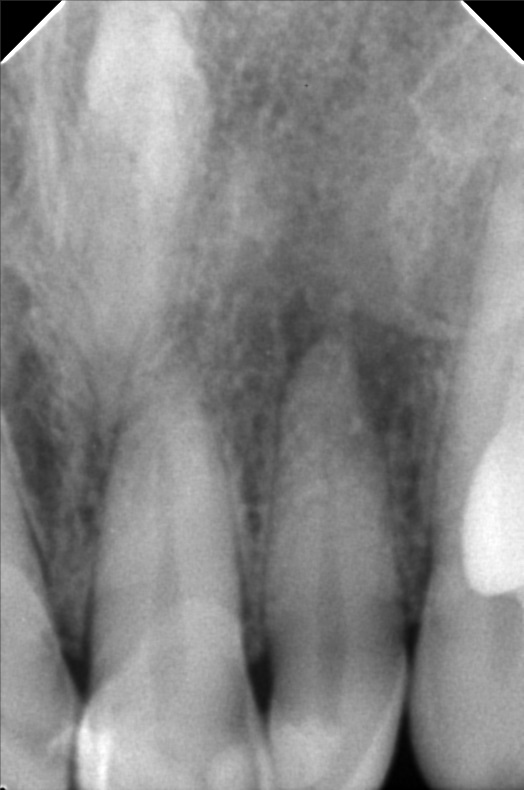

- 10/05/21 -0p/ Lc 11m/21M *22 subject for rct *11 distal repeat lc/ 21 repeat lc/ 12 lingual repeat lc 10/15/21- rct 22mm/ apical abcess laser done apexcal 10/22/21 - LC #12 mesial #11 Lc Distal #21 Distal LC #22 veneer #22 obturate- 22mm guttaflow 04/02/22- veneer due to spaces #41/42/43/31/32/ shade A3/ esthetica 08/25/2023- Cleaning veneer re-polish 11/12/22/21

- bonifacio1.jpg

- bonifacio2.jpg

- bonifacio3.jpg

- 22bonifacio101521.jpg